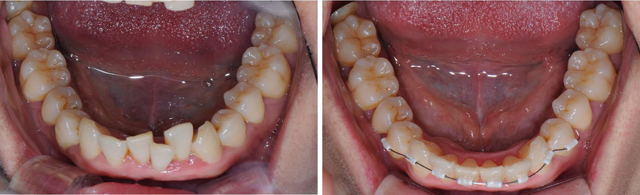

MTA 교정치료(앞니부분교정)

최신 미니튜브장치를 이용하여 짧은 기간 내에 불편감을 최소로하여 심미적인 전치부 배열을 얻는 교정술식입니다.

치료전

치료 3개월후